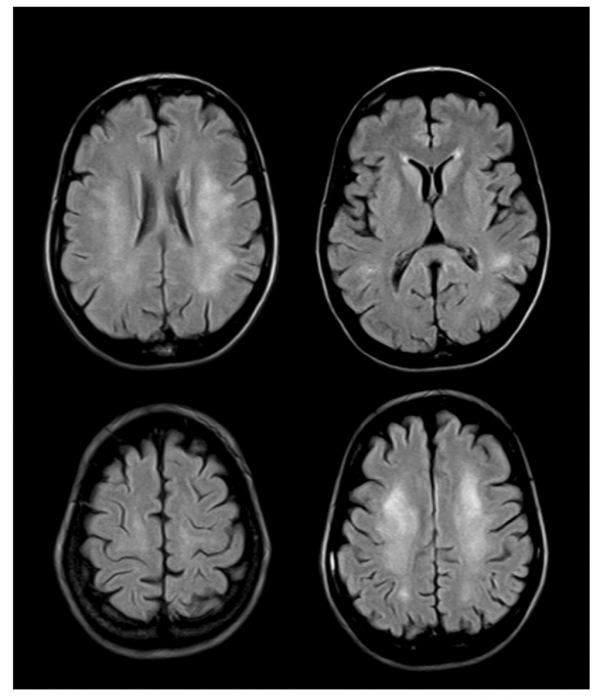

- Изменения в позвонках и межпозвоночных дисках могут быть выявлены с помощью МРТ, что позволяет оценить состояние позвоночника и своевременно начать лечение.